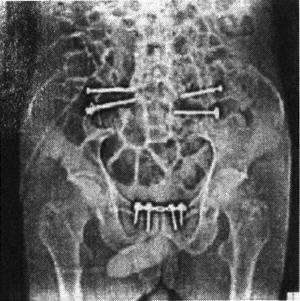

图13-60 Depuy的ISOLA骶髂关节螺钉

图13-61 骶髂关节螺钉固定术后X光片